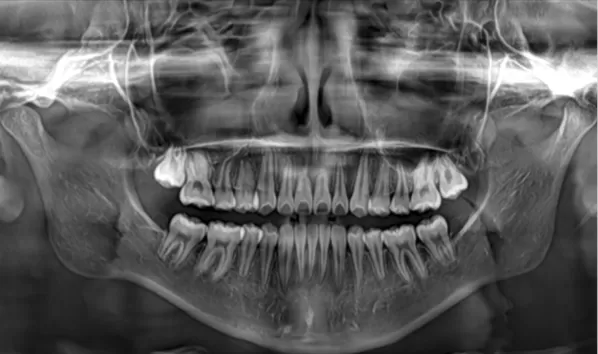

Rayons X avant le traitement

[Radiographie panoramique/Céphalogramme latéral]